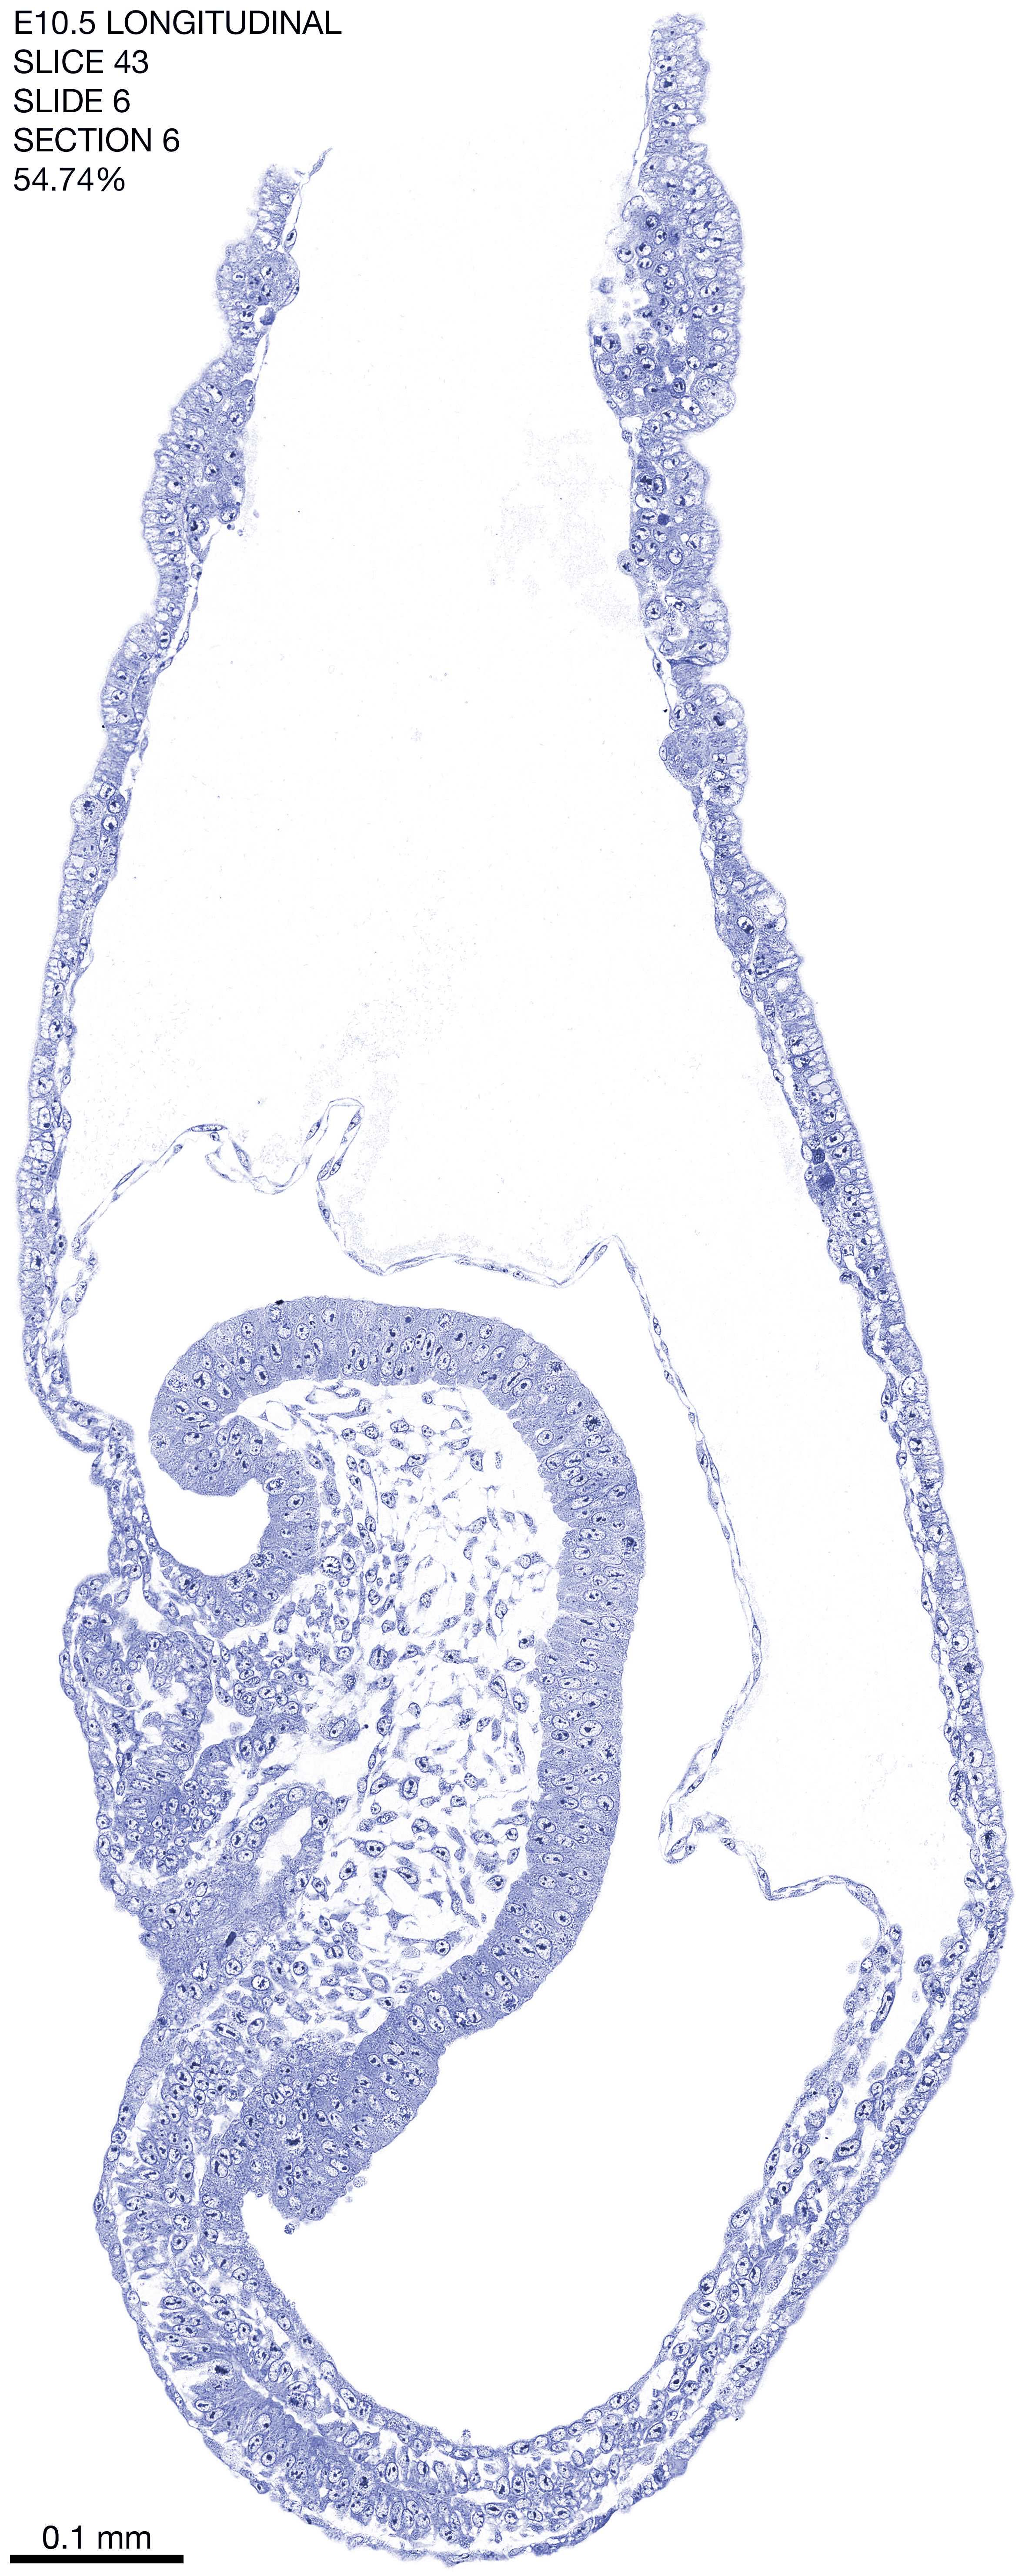

E10.5 Longitudianal Archive This page contains jpg files of ALL SLICES (each 3µm thick) that were scanned of the E10.5 longitudinally cut specimen. Download: Large | High Res Download: Large | High Res Download: Large | High Res Download: Large | High Res Download: Large | High Res Download: Large | High Res Download: Large | High Res Download: Large | High Res Download: Large | High Res Download: Large | High Res Download: Large | High Res Download: Large | High Res Download: Large | High Res Download: Large | High Res Download: Large | High Res Download: Large | High Res Download: Large | High Res Download: Large | High Res Download: Large | High Res Download: Large | High Res Download: Large | High Res Download: Large | High Res Download: Large | High Res Download: Large | High Res Download: Large | High Res Download: Large | High Res Download: Large | High Res Download: Large | High Res Download: Large | High Res Download: Large | High Res Download: Large | High Res Download: Large | High Res Download: Large | High Res Download: Large | High Res Download: Large | High Res Download: Large | High Res Download: Large | High Res Download: Large | High Res Download: Large | High Res Download: Large | High Res Download: Large | High Res Download: Large | High Res Download: Large | High Res Download: Large | High Res Download: Large | High Res Download: Large | High Res Download: Large | High Res Download: Large | High Res Download: Large | High Res Download: Large | High Res Download: Large | High Res Download: Large | High Res Download: Large | High Res Download: Large | High Res Download: Large | High Res Download: Large | High Res Download: Large | High Res Download: Large | High Res